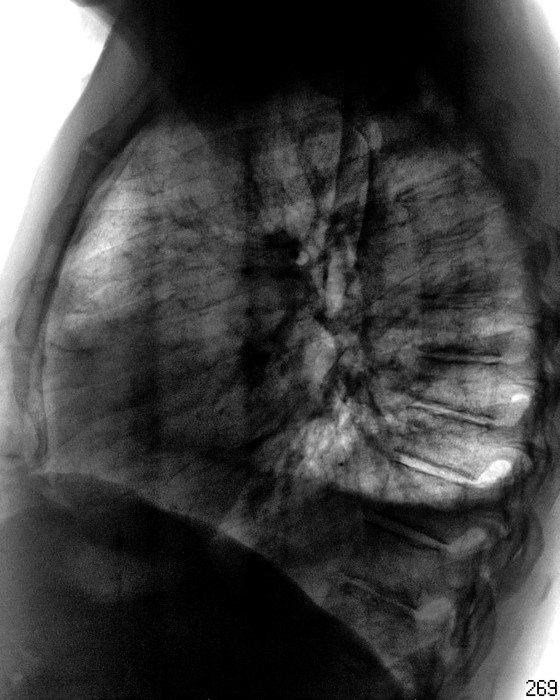

Пол пациента: Мужской пол Тип патологии: Другое Область исследования: Грудная клетка и верхние дыхательные пути Методы исследования: Rg Направлен на рентгенографию ОГК с подозрением на левостороннюю пневмонию. 2. https://radiomed.ru/sites/default/files/styles/case_slider_image/public/user/12/12.201411050032.jpg?itok=dJ8_3Oxo https://radiomed.ru/sites/default/files/styles/case_slider_image/public/user/12/13.201411050033.jpg?itok=fmadLMvN ID:56752 Пт, 07/11/2014 - 15:23 #1 NIL Не на сайте Был на сайте: 6 часов 38 минут назад Зарегистрирован: 25.11.2013 - 20:50 Публикации: 18206 Гидроторакс слева, на фоне которого что-то шаровидное. Латерографию бы (для начала). "Слушай всех, прислушивайся к немногим, решай сам".© Пт, 07/11/2014 - 16:26 #2 Сергей Кузьминов Не на сайте Был на сайте: 1 год 2 недели назад Зарегистрирован: 06.10.2012 - 15:51 Публикации: 11813 Нет.Для начала-контроль после пункции. Пт, 07/11/2014 - 21:20 #3 И.Бондаренко Не на сайте Был на сайте: 2 дня 5 часов назад Зарегистрирован: 13.09.2011 - 22:55 Публикации: 9206 +1 Пнд, 10/11/2014 - 12:36 #4 Катенёв Валенти... Не на сайте Был на сайте: 7 лет 2 недели назад Зарегистрирован: 22.03.2008 - 22:15 Публикации: 54876 "Шаровидное" - по боковой? Пнд, 10/11/2014 - 12:54 #5 NIL Не на сайте Был на сайте: 6 часов 38 минут назад Зарегистрирован: 25.11.2013 - 20:50 Публикации: 18206 И на прямой тоже естьПриложения: "Слушай всех, прислушивайся к немногим, решай сам".© Пнд, 10/11/2014 - 12:56 #6 Катенёв Валенти... Не на сайте Был на сайте: 7 лет 2 недели назад Зарегистрирован: 22.03.2008 - 22:15 Публикации: 54876 Если по прямой, так с другой стороны точно такой...

Гидроторакс слева, на фоне которого что-то шаровидное. Латерографию бы (для начала).

"Шаровидное" - по боковой?

И на прямой тоже есть

Если по прямой, так с другой стороны точно такой...